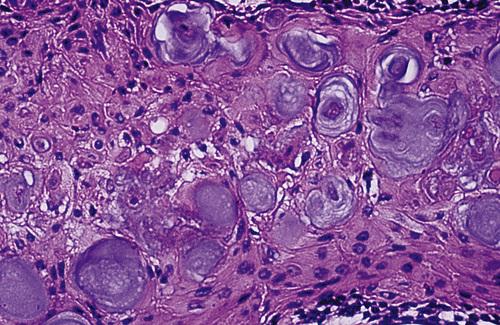

The cyst lining shows ameloblastoma-like epithelial cells, with a columnar basal layer. Large eosinophilic ghost cells are present within the epithelial lining.

calcifying odontogenic cyst